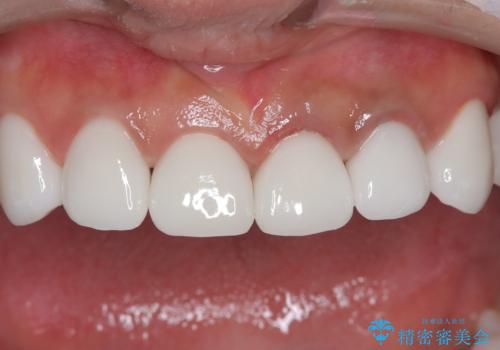

【オールセラミッククラウン】前歯を白くきれいにしたい。

- 前歯の変色を主訴に来院されました。

歯茎のラインも整っていなかったため、手術を行いきれいな被せ物をいれることができました。

歯茎のラインを整える手術を行ったあとは、しばらく待ってから被せ物の治療を行っていきます。